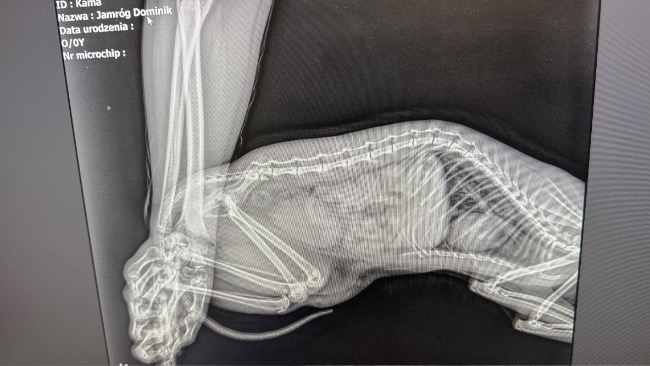

[28.03] Byłyśmy wczoraj z Kamą na wizycie kontrolnej u dr. Konopki. Rana pooperacyjna wygląda idealnie, wszystko goi się tak jak powinno. W tym momencie rokowania są optymistyczne, Kami ma czucie w łapkach i (koślawo) porusza się na nich. Pozostaje nam tylko rekonwalescencja i ograniczenie ruchu do minimum. Kicia ma teraz swoje miejsce w klatce kenelowej. Przed nami jeszcze kilkanaście dni podawania antybiotyku, probiotyku i gabapentyny. Po świętach wybieramy się na ściąganie szwów ☺️